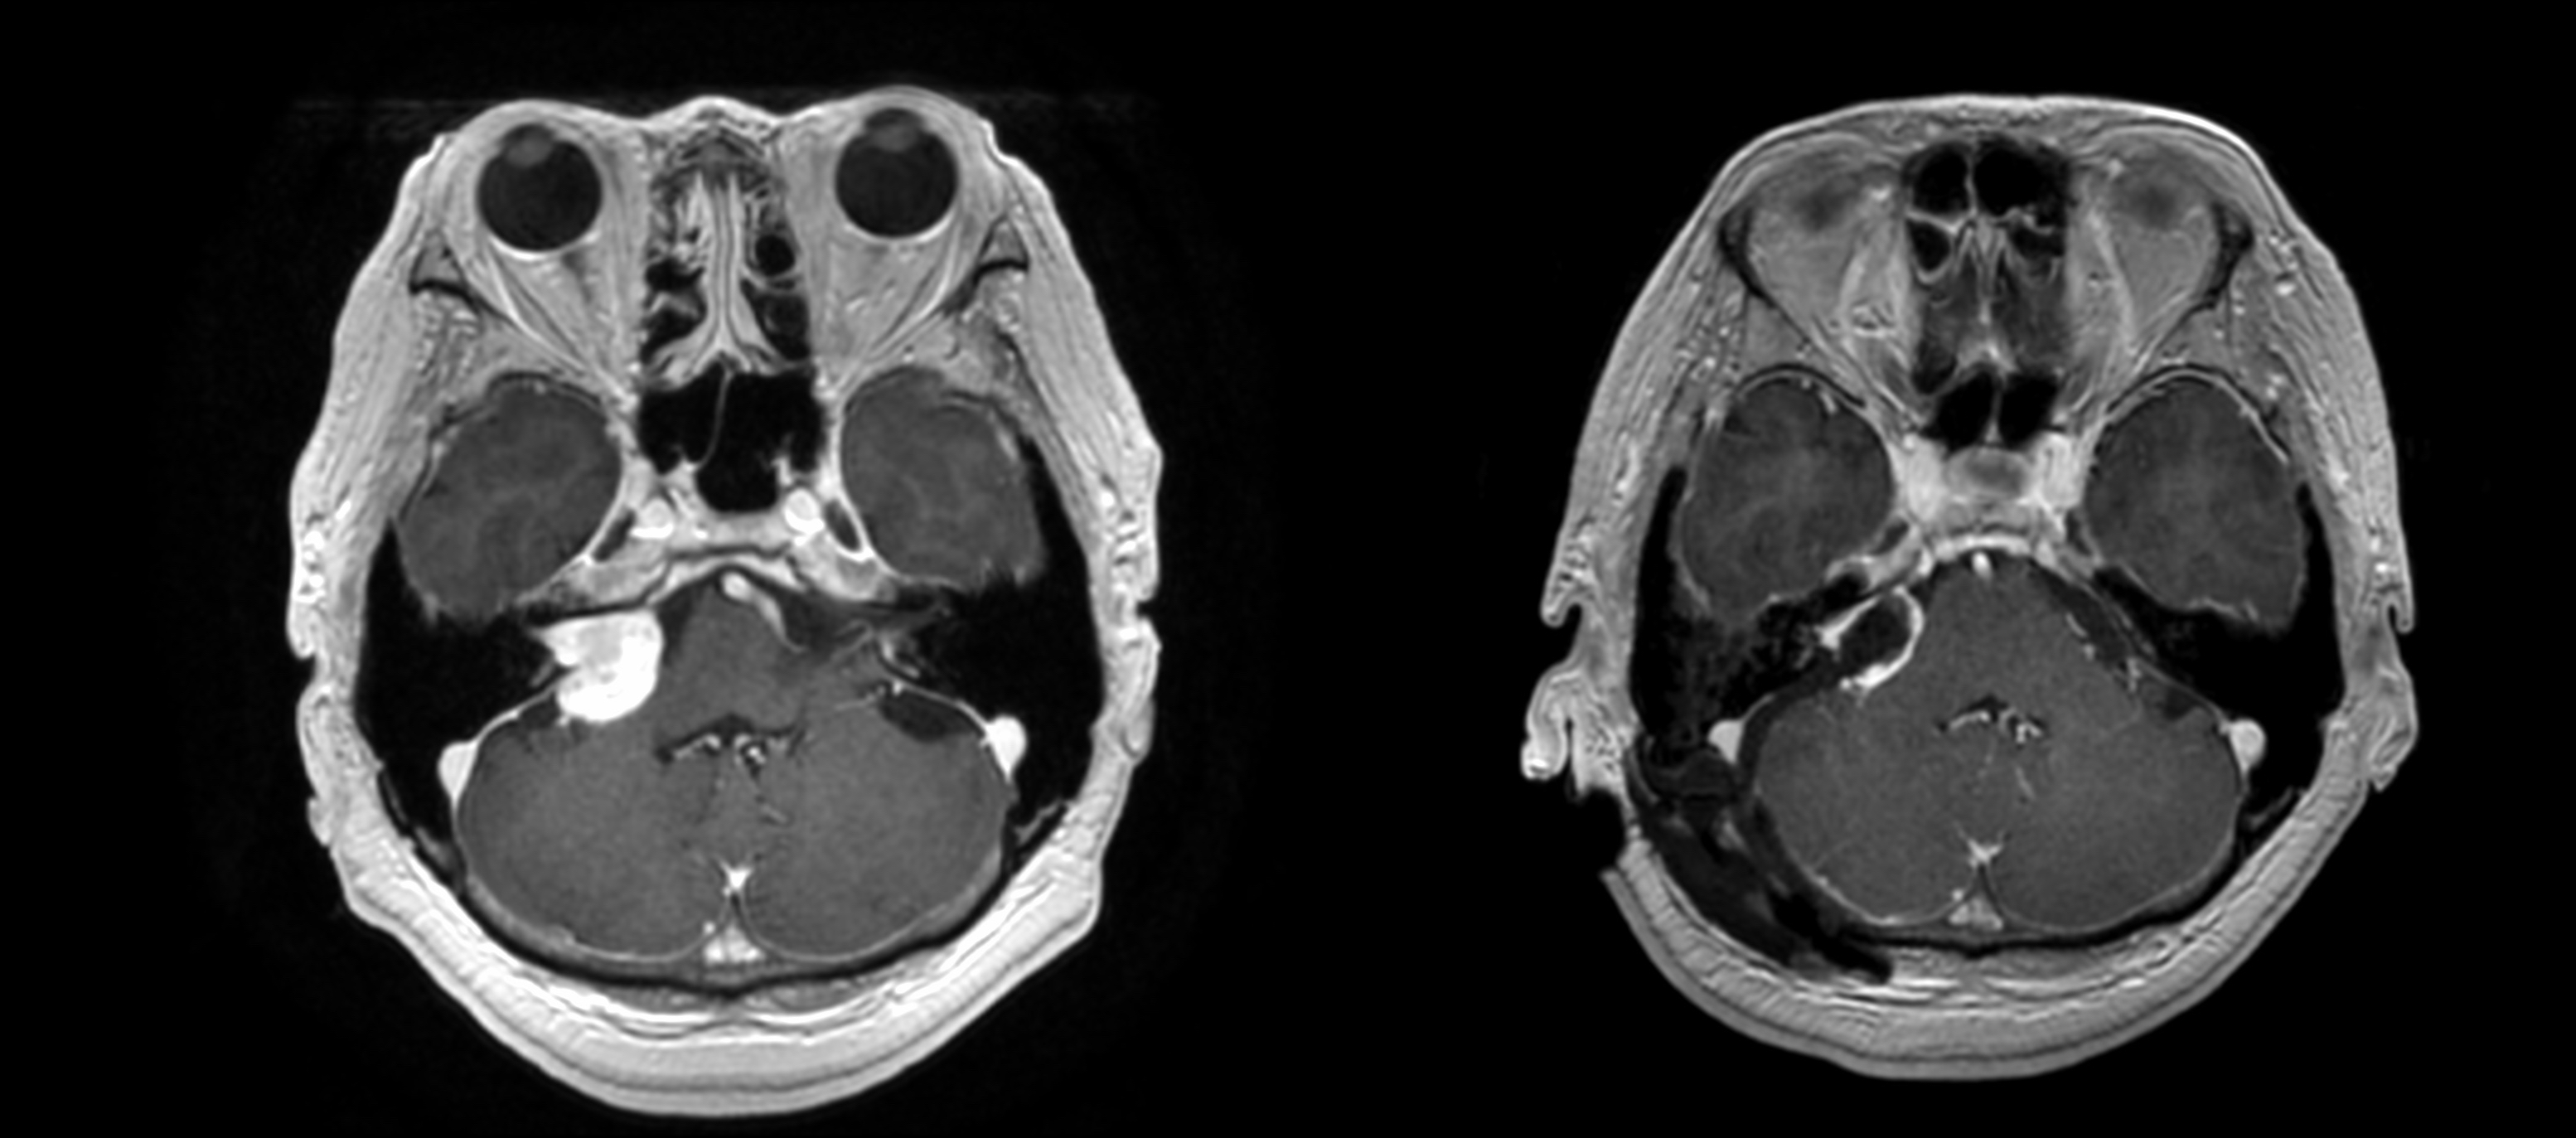

- 腫瘍の位置を特定するためのCT、MRI、陽電子放出断層撮影法(PET)スキャンなどの画像検査